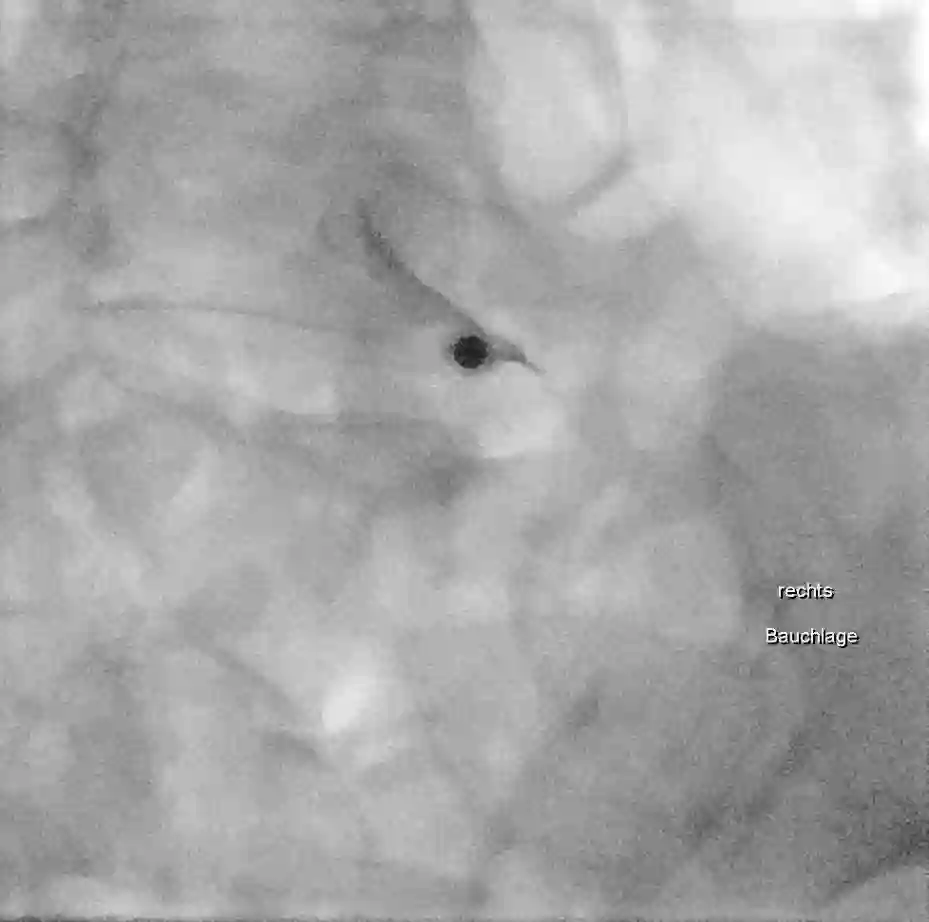

Bei einer Nervenwurzelinfiltration, oder auch Nervenblockade genannt, wird unter einer Bildgebung (Ultraschall, Durchleuchtung oder CT) eine Mischung aus Lokalanästhetikum, mit oder ohne Kortison direkt an die Nervenwurzel appliziert. Man unterscheidet zwischen einer therapeutischen und diagnostischen Infiltration.

- Durchführung einer Nervenwurzelinfiltration der Nervenwurzel C7 links mithilfe des CTs.